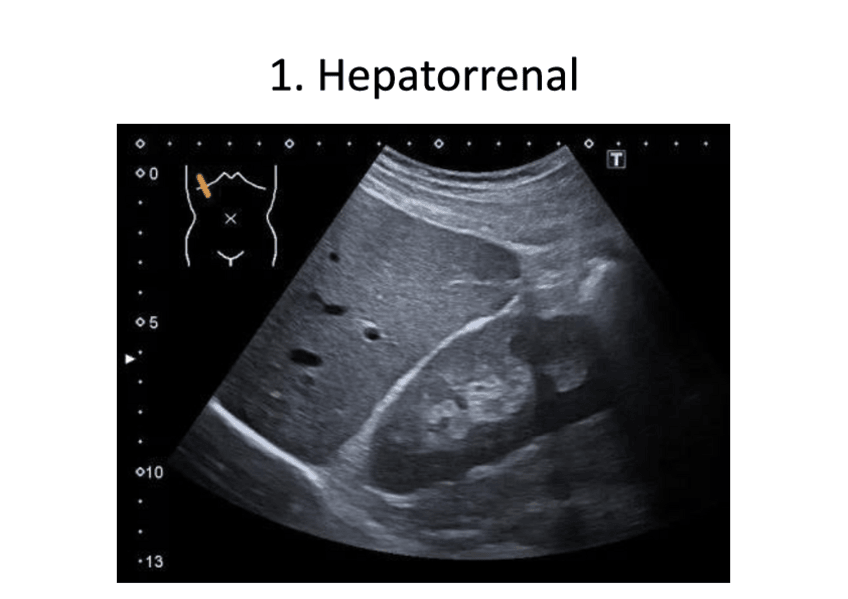

He publicado nuevos trabajos de 2º Imagen Médica e Instrumentación: Casos-Ecograficos.pdf